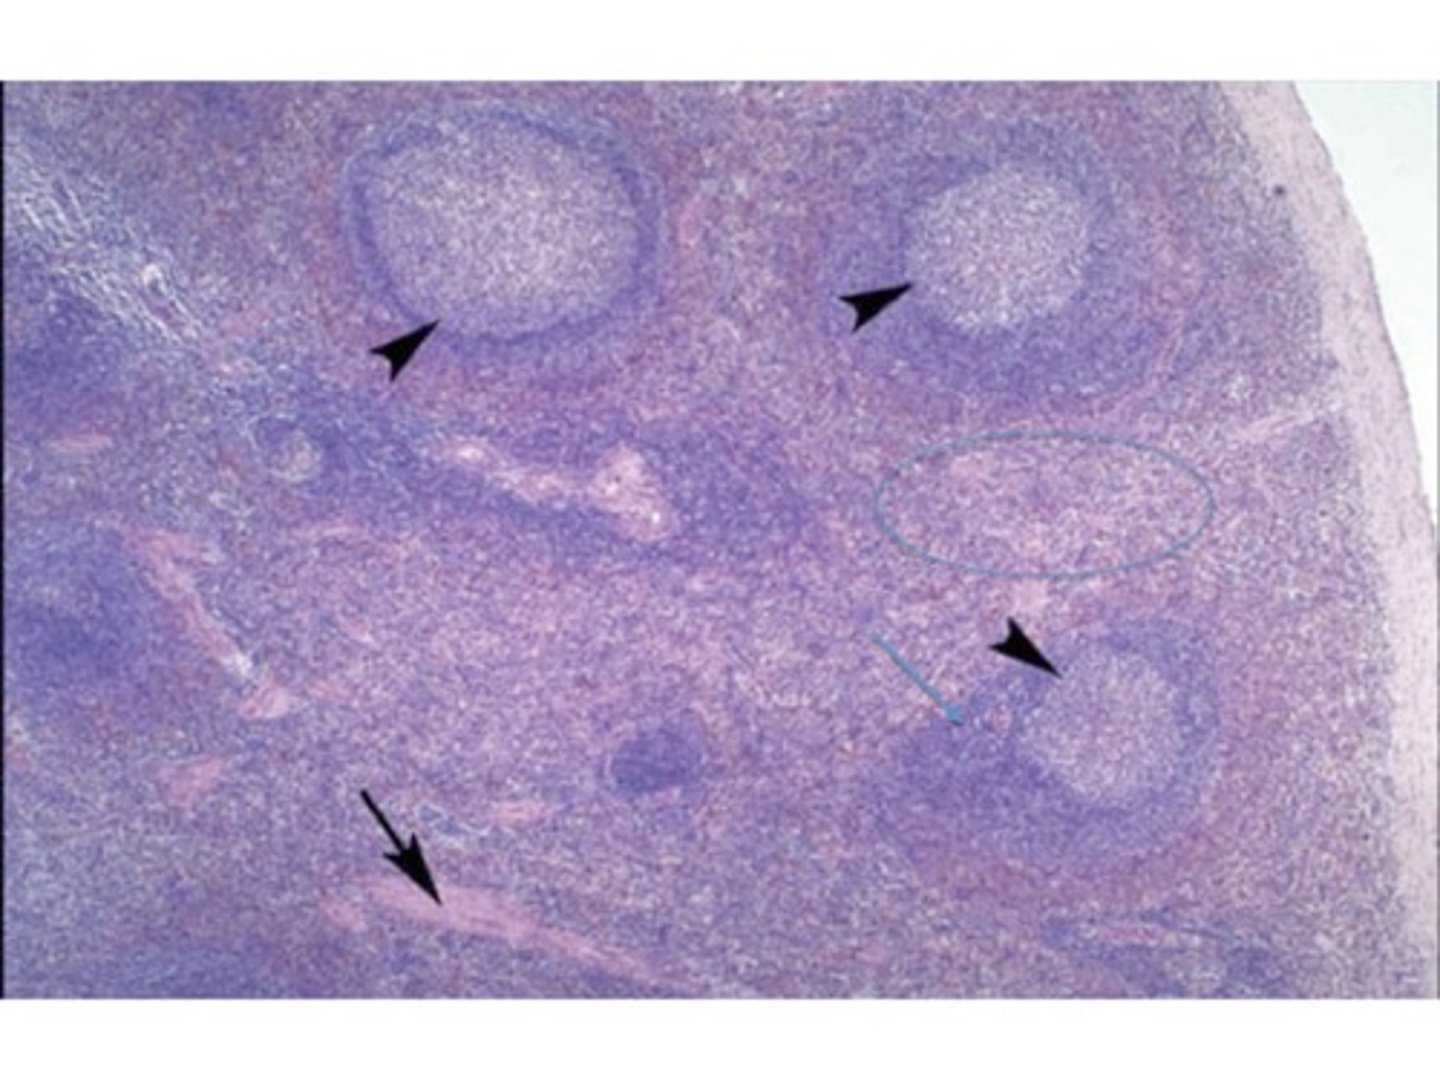

lymphatic capsule (lymph node)

The connective tissue that surrounds and protects the lymph node.

trabeculae (lymph node)

the extends inward and partition the interior of the node.

cortex (lymph node)

Contains clusters of lymphocytes. The outer region of a lymph node containing B cells, dendritic cells, and macrophages, playing a key role in immune response activation.

sinuses (lymph node)

spaces allowing lymph movement through the node

medulla (lymph node)

Medullary cords extend inward from cortex and contain B cells, T cells, and plasma cells

medullary cords (lymph node)

lymphatic tissue in the medulla of a lymph node filled with B cells, plasma cells, and macrophages, playing a role in antibody production and immune response.